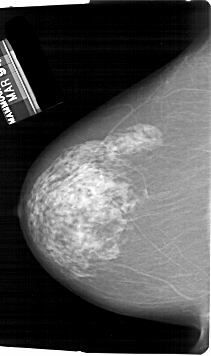

A_1829_1.LEFT_MLO

ics_version 1.0

filename A-1829-1

DATE_OF_STUDY 10 3 1994

PATIENT_AGE 71

FILM_TYPE REGULAR

DENSITY 3

DATE_DIGITIZED 15 6 1998

DIGITIZER HOWTEK 43.5

LEFT_MLO LINES 6676 PIXELS_PER_LINE 4171 BITS_PER_PIXEL 12 RESOLUTION 43.5 NON_OVERLAY